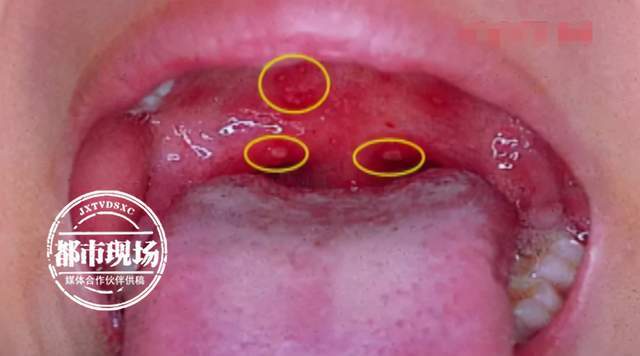

孩子突然发烧咽喉痛医生不是普通感冒最近高发家长要重视

图片尺寸640x356

诊间日记##疱疹性咽峡炎